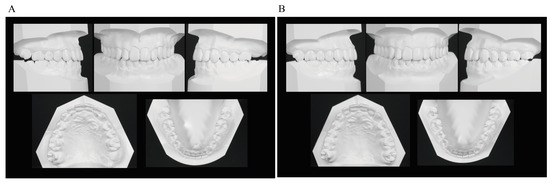

In the frontal view, the midline deviation seen at the initial presentation was corrected, with the maxillary and mandibular midlines aligned with the facial midline. In the lateral view, a good E-line was maintained. The occlusal relationship of the first molars was Angle Class I on both sides, demonstrating close occlusion. The maxillary left canine that had shown eruption disturbance was aligned in the dental arch. The maxillary left third molar naturally erupted and occluded with the mandibular left second molar. The maxillary and maxillary anterior teeth were in an appropriate covering relationship (Figure 7 and Figure 8).

Panoramic radiographs showed good root parallelism, no root resorption in the tractioned maxillary left canine or other teeth, and no abnormalities in the periodontal tissue. The maxillary left third molar, which had been impacted when active treatment was terminated, fully erupted 3 years and 6 months after active treatment was terminated. The maxillary right third molar and mandibular right and left third molars are impacted and scheduled for extraction (Figure 9).

Lateral cephalometric radiography showed the following changes in the anteroposterior position of the maxillary first molars before and after the use of the Hyrax-type expander: A′-Ms from 32.5 mm to 33.0 mm for the right and from 28.0 mm to 33.0 mm for the left, and ptm′-Ms from 18.5 mm to 19.0 mm for the right and from 23.0 mm to 19.0 mm for the right. Thus, the right first molar showed no change in position while the left first molar was moved distally by about 4.5 mm to almost the same position as the right one. The axial inclination angle of the right maxillary first molar was unchanged from 83.0° while that of the left first molar decreased from 88.0° to 83.0°, indicating that the mesially inclined left first molar was caused to slightly incline distally (Figure 10 and Table 1).

When active treatment was terminated, SNA was increased by 0.5° compared with before active treatment was terminated due to anterior maxillary growth. Although point B was retracted, the SNB was unchanged at 88.5° due to anterior mandibular growth, which resulted in a 0.5° increase in ANB. Vertically, FMA was increased by 0.5°, indicating a slight clockwise rotation of the mandible. U-1 to NA increased to 4.0 mm/22.5°, indicating labial tipping movement of the maxillary central incisor, while the L-1 to NB increased to 4.0 mm/20.5°and the FMIA decreased from 80.5° to 73.5°, indicating labial tipping of the mandibular central incisor. This resulted in the improvement of the interincisal angle to 135.5° (Figure 11 and Table 1).

At completion of eruption of the maxillary left third molar, there was a slight skeletal change (ANB: 0.5° decrease; FMA: 0.5° decrease) from the termination of active treatment, but there was no change in the position of the maxillary and mandibular anterior teeth and the maxillary first molar (Figure 12 and Table 1).

Figure 8. Dental casts. (A) At termination of active treatment (age, 17 years 9 months). (B) At completion of eruption of the maxillary left third molar (age, 21 years 3 months).